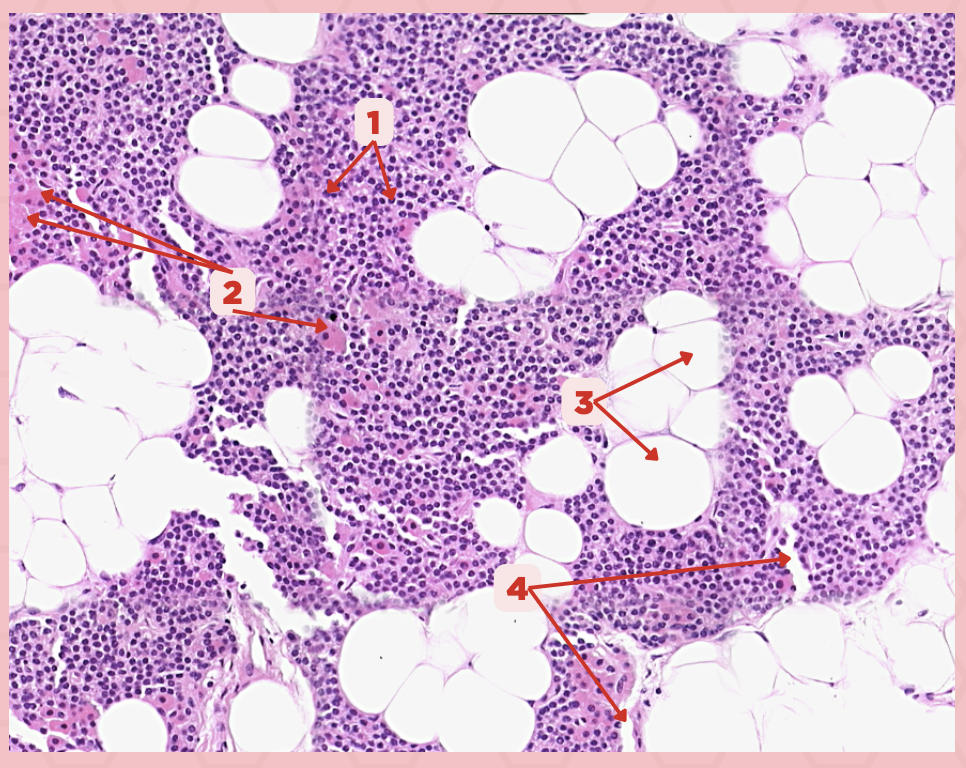

Parathyroid

Identify the specimen.

Chief Cells

Identify the structure labeled as 1. This comprise the majority of cells in the parathyroid gland.

Septa

Identify the structure labeled as 2.

Parathyroid hormones

What hormones are synthesized and secreted by the cell in Pointer #1?

Oxyphil cells

What parenchymal cells in the parathyroid gland only appear shortly before puberty and increase in number with age?

Parathyroid

Identify the specimen.

Chief Cells

Identify the specimen labeled as 1.

Oxyphil Cells

Identify the specimen labeled as 2.

Adipocytes

Identify the specimen labeled as 3.

Capillaries

Identify the specimen labeled as 4.

Newborns

Pointer #2 is hardly present in the parathyroid glands of _____.